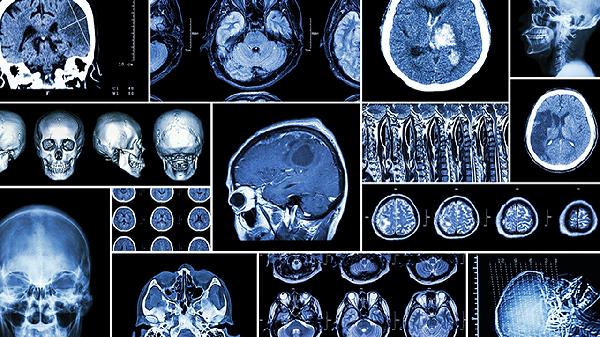

大脑逻辑思维功能区主要位于前额叶皮层,尤其是背外侧前额叶和腹外侧前额叶。逻辑思维涉及多个脑区的协同工作,包括顶叶、颞叶以及基底神经节等。

前额叶皮层是逻辑思维的核心区域,负责高级认知功能。背外侧前额叶参与工作记忆和问题解决,腹外侧前额叶与规则学习和决策制定相关。前额叶损伤可能导致计划能力下降和抽象思维障碍。

顶叶特别是上顶叶参与空间推理和数学运算。该区域帮助整合视觉空间信息,在几何证明和逻辑推理中起重要作用。顶叶损伤可能影响对复杂关系的理解能力。

颞叶与语言理解和概念形成密切相关。左侧颞叶负责语义处理,在逻辑论证中帮助理解前提和结论的关系。颞叶损伤可能导致逻辑语言表达障碍。

基底神经节参与程序性学习和习惯形成。在逻辑思维中帮助自动化简单推理过程,释放前额叶资源处理复杂问题。帕金森病患者常表现出逻辑思维速度减慢。

逻辑思维依赖默认模式网络与执行控制网络的动态交互。前额叶-顶叶-颞叶形成的三角回路支持抽象推理,白质纤维束保证各脑区信息传递效率。